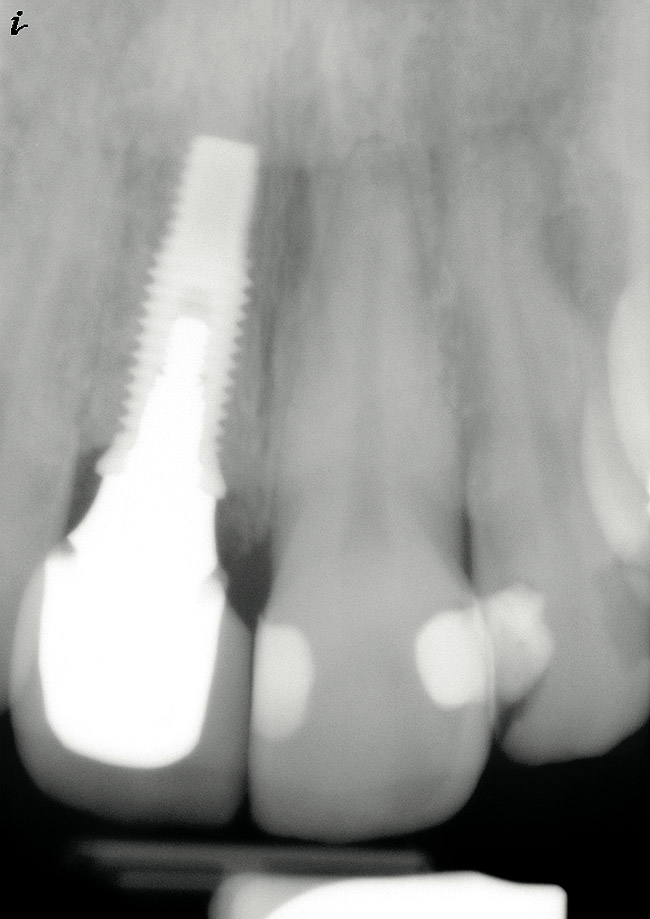

Figure 13  Postoperative findings were consistent with normal bone remodeling and implant integration.

Figure 13

In the present case, a submarginal incision was made at the mucogingival gingival junction, revealing the facial fenestration defect (Figure 10 ). The mucosa was elevated to access and graft both the socket and fenestration defect. Both sites were protected by a collagen membrane (Bio-Gide®), and sutured to close the submarginal incision (Figure 11 ). Medical cyanoacrylate was placed over the socket wound to stabilize the collagen membrane. Healing was uneventful, and the soft-tissue contours suggested preservation of the alveolar contours at the time of extraction. Five months after extraction and augmentation, the findings from a clinical postoperative radiograph demonstrated evidence of notable graft containment as reflected by the overall radiopacity of the extraction site, even coronal to the socket. The site was reentered for implant placement. Flap elevation revealed the dense bone ridge with complete incorporation of the particulate graft material. The osteotomy for implant placement was prepared with a trephine bur, and the resulting specimen was submitted for histologic evaluation. The histologic findings revealed evidence of robust osteogenesis throughout the bone core, including the coronal aspect supporting the soft tissue. New bone was found in close amalgamation with the FDBA-graft particles throughout the specimen. A dental implant was placed at the site in a single-stage surgery and allowed to heal for 5 months prior to the restoration. The esthetic outcome was highly acceptable, with preservation of the marginal and papillary gingiva contours (Figure 12 ). The radiographic findings showed consistent normal bone remodeling and implant integration (Figure 13 ).